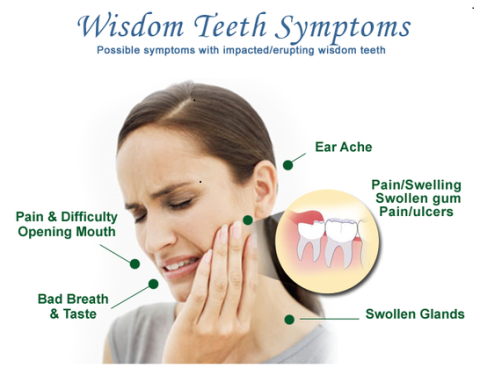

Wisdom teeth are the last tooth behind the upper and lower second molars, and usually appear during a person's late teens or early twenties. When a wisdom tooth is blocked from erupting or coming into the mouth in its normally position, it is termed "impacted"

Serious problems may develop from impacted teeth, such as pain, infection, crowding of, or damage to adjacent teeth. Sometimes more serious problems can occur if the sac that surrounds the impacted tooth fills with fluid and enlarges to form a cyst. This enlargement can hollow out the jaw and result in permanent damage to the adjacent teeth, jawbone and nerves. If the cyst is not treated, a tumor may develop from the walls of the cyst and a more involved surgical procedure may be required for removal. Many problems with wisdom teeth may occur with few or no symptoms, so there may be damage without you knowing it.